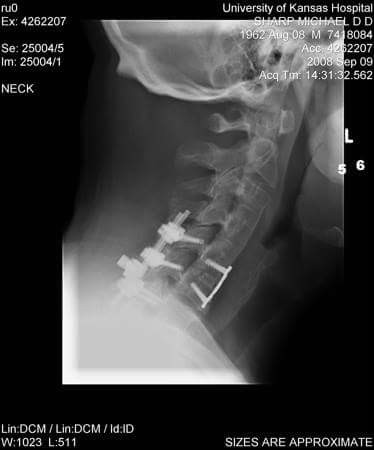

At age 45, after 14 surgeries from the accident, 4 of those cervical spine fusions from the severe whiplash in the accident. I had to have an additional neck surgery two years after I was on full disability. The hardware place in the back of my neck in the 3rd cervical fusion there was a rod poking one inch in my neck muscle for 3 years. I had had over 20 epidurals and trigger point injections. A year after I was on disability a driver of a Ford F150 RAN A RED LIGHT AND t-bone my tiny PT CRUISER and I hit my head on the car FRAME because my torso is so long. I lost most of my present memory from that point on but I have retained my long term photographic memory. I try to help other chronic pain patients as best I can online.